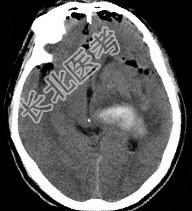

- 单项选择题男,32岁, 外伤后一天,CT检查如图, 下面何项诊断最恰当 ( )

A、脑出血

B、颅脑外伤

C、颅内积气

D、脑膜瘤

E、脑出血并颅内积气